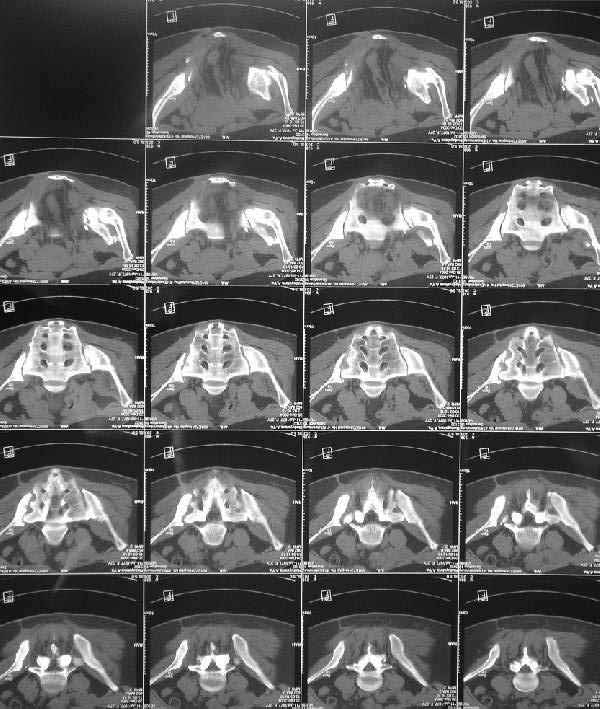

X-rays and more CT - see attached.

![]() |